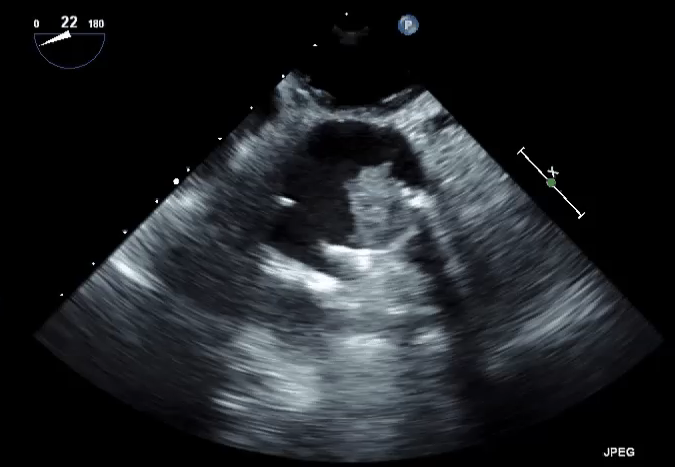

A 19-year-old woman presents with signs and symptoms of heart failure (HF) at 33 weeks gestation of her first pregnancy. The patient was born with truncus arteriosus and underwent ventricular septal defect closure, right ventricle-to-pulmonary artery conduit placement in infancy, with subsequent conduit and mechanical aortic valve replacement as an adolescent. Due to the pregnancy, she was switched from warfarin 10 mg daily to low-molecular-weight heparin at week 6 of gestation. Four months prior to this presentation, while on heparin but with variable compliance, she was hospitalized with a deep venous thrombosis of the right common femoral vein. This was managed conservatively. On this current presentation, she reports 3 weeks of progressive dyspnea on exertion, fatigue, and lower extremity edema that limit her activity. She reports no chest pain, presyncope, syncope, or palpitations. Vital signs are within normal limits. The exam is notable for mild lower extremity edema, a harsh IV/VI systolic ejection murmur at the cardiac base, and a I/IV high-pitched decrescendo diastolic murmur at the apex. Significant laboratory results include 95,000 platelets, B-type natriuretic peptide 273pg/mL, and anti-Xa level 0.62 (goal 0.8-1.2 units/mL). Figures 1 and 2 below are from the transthoracic echocardiogram. Previous baseline aortic valve velocity was 3.8 m/s. A cine clip from aortic valve fluoroscopy is shown in Video 1.

Figure 1: Color Doppler Across the Aortic Valve